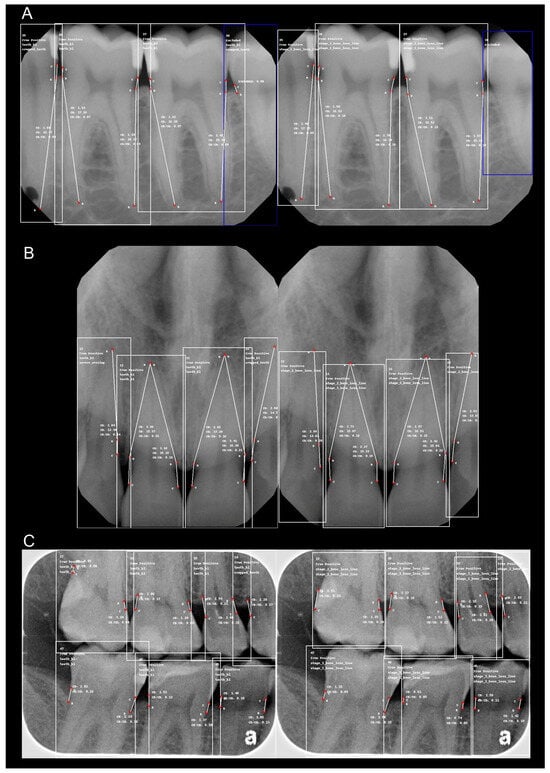

Figure 1 presents comparative examples, illustrating the reference standard (left) and model predictions (right) for key points and measurements in posterior periapical radiographs (a), anterior periapical radiographs (b), and bitewing radiographs (c).

Figure 1. Comparative samples of radiographic bone loss (RBL) detection: reference standard versus model predictions. Images on the left represent the reference standard annotations, while images on the right display model-predicted points and measurements. (A) Posterior periapical radiographs, (B) anterior periapical radiographs, and (C) bitewing radiographs. Each image illustrates key anatomical landmarks, including the cementoenamel junction (CEJ), bone level, and root apex, used to assess RBL. In periapical radiographs, the CEJ is labeled as (C), bone level as (B), and root apex as (R), while in bitewing radiographs, only (C) and (B) are annotated.